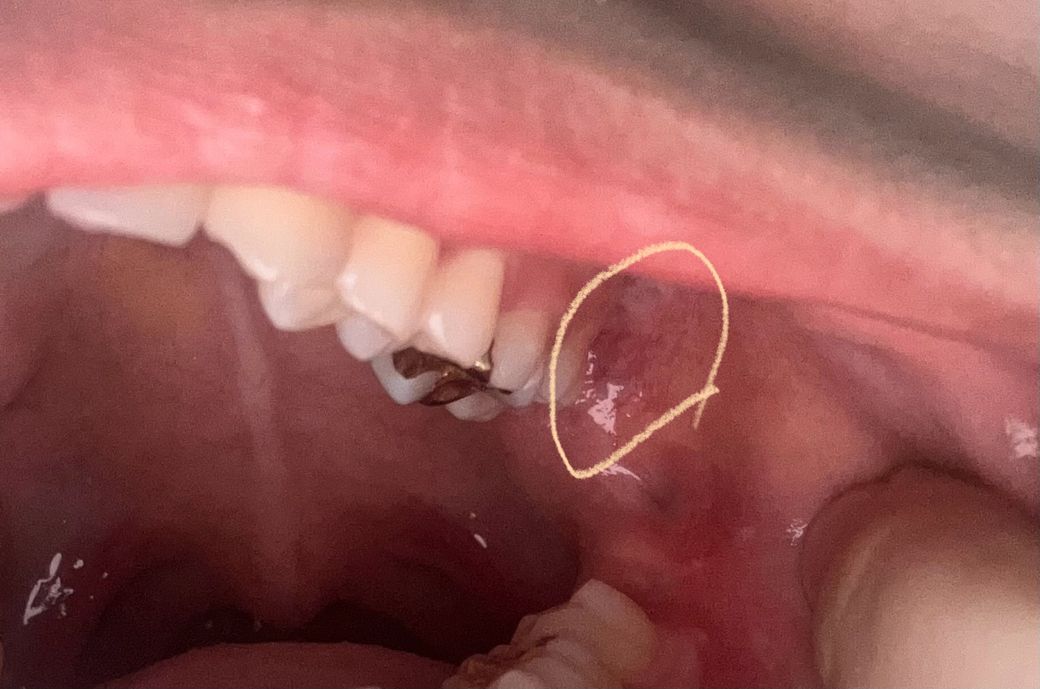

구강편평태선인가요 오른쪽은 조금 하얗긴한데 핏줄도 잘 보이지않는데 왼쪽 어금니뒤쪽은 핏줄들도 너무 두드러지게보이고 그쪽이 하얗게 됐습니다 그물모양은 아닌것같은데 선처럼 쭉 되어있습니다

• 2번 째 사진

사진상으로 보이는건 편평태선은 아니고 볼살이 치아에 눌렷거나 자극을 받아서 생긴 자국같습니다.

편평태선은 다양한 양상이 나타날 수 있습니다 편평태선 외에도 구강 내 병소가 의심되니 구강내과가셔서 조직검사를 받아보시면 좋을 것 같습니다